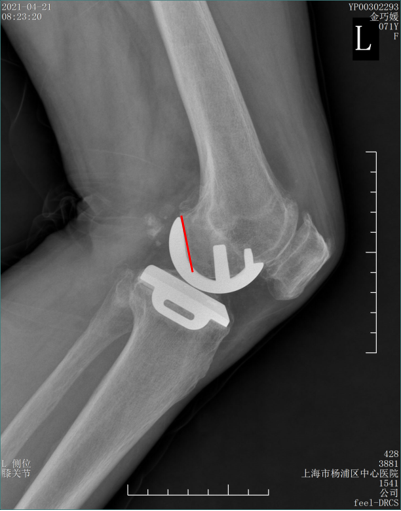

病例2:Bearing 破裂( X-ray正位)

解读:两个点都在内侧

病例2:Bearing 破裂( X-ray侧位)

解读:股骨假体与胫骨假体间隙还存在,在图像放大4倍情况下,才依稀看到模糊的点.

病例2:Bearing 破裂

病例2:Bearing 破裂的处理